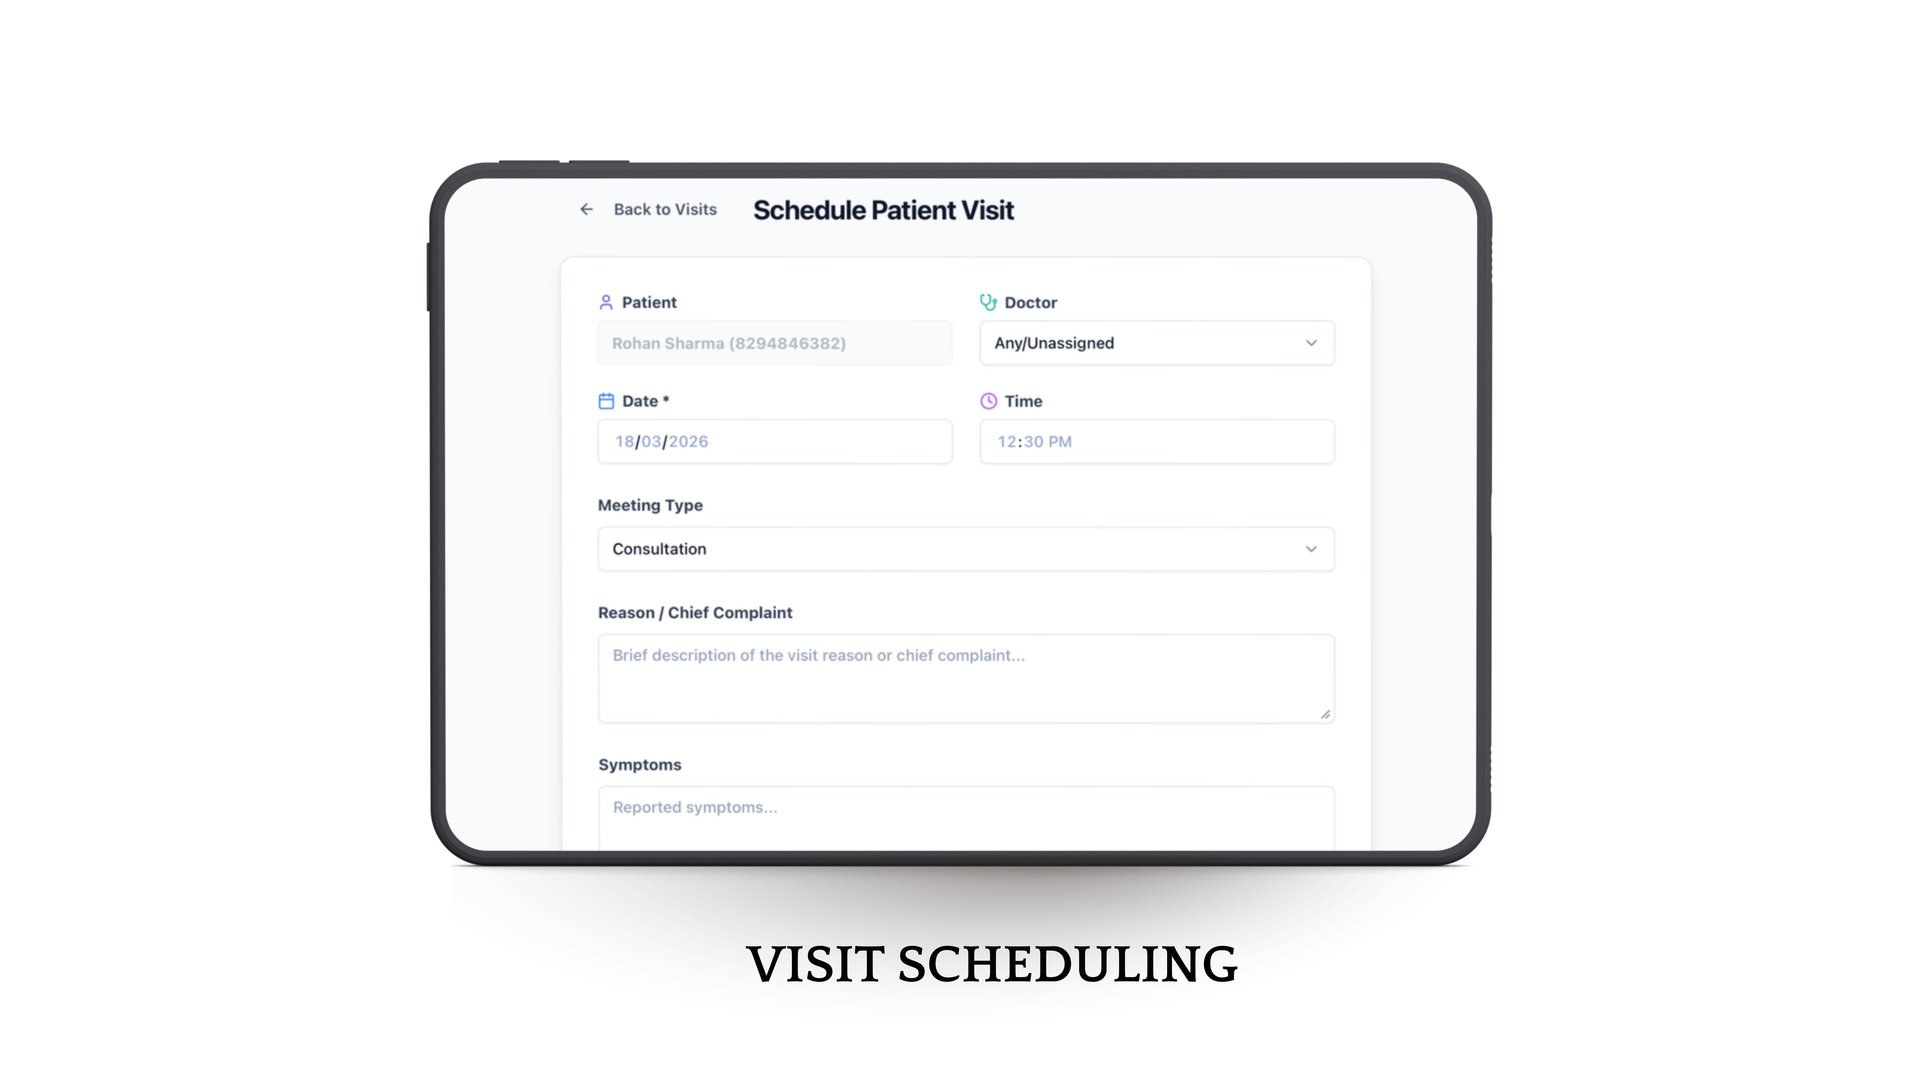

It simplifies everything—from patient entry to follow-up

Easy OPD workflows in few taps.

From better tracking to personalized care journeys, Phia.Care helps deliver a smoother, more connected experience for every patient.